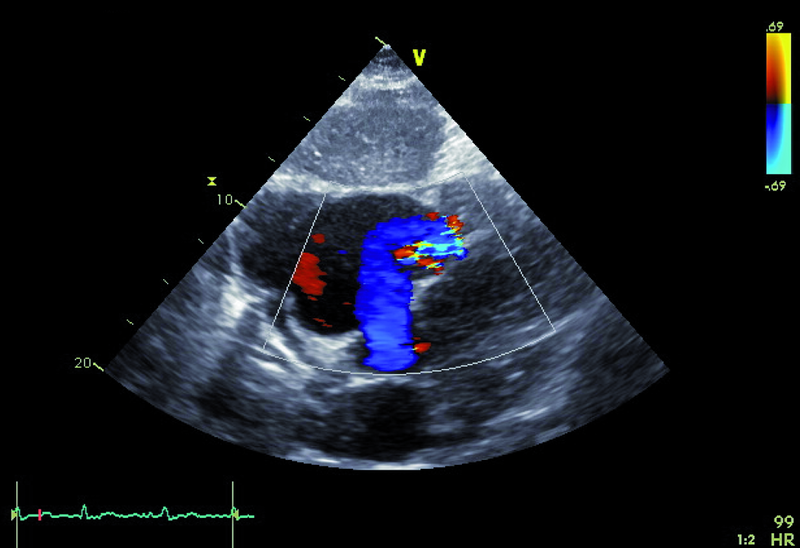

Kobieta, lat 73. Jakie patologie można rozpoznać na rycinach?

1. Ubytek przegrody międzyprzedsionkowej typu II (ryc. 1).

2. Niedomykalność zastawki trójdzielnej (ryc. 1).